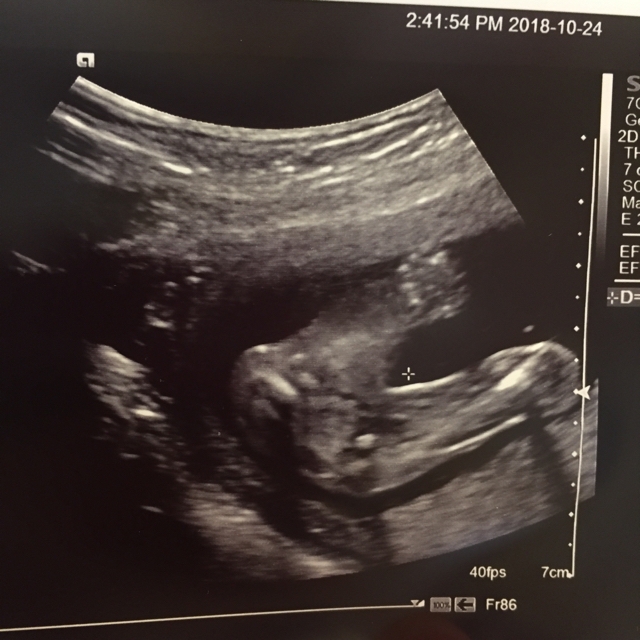

妊娠19週4日エコー動画 19w4d Echo Video Pregnancy Youtube

妊娠20週目 20w0d 6d のエコー写真とエピソード 妊娠6ヶ月 Cozre コズレ 子育てマガジン

妊娠19週目 胎動や性別が分かる人も 胎児のエコー写真 大きさ 妊娠中期 All About

妊娠20週目エコー写真 胎児の大きさや胎動の様子 性別 妊娠中期 All About